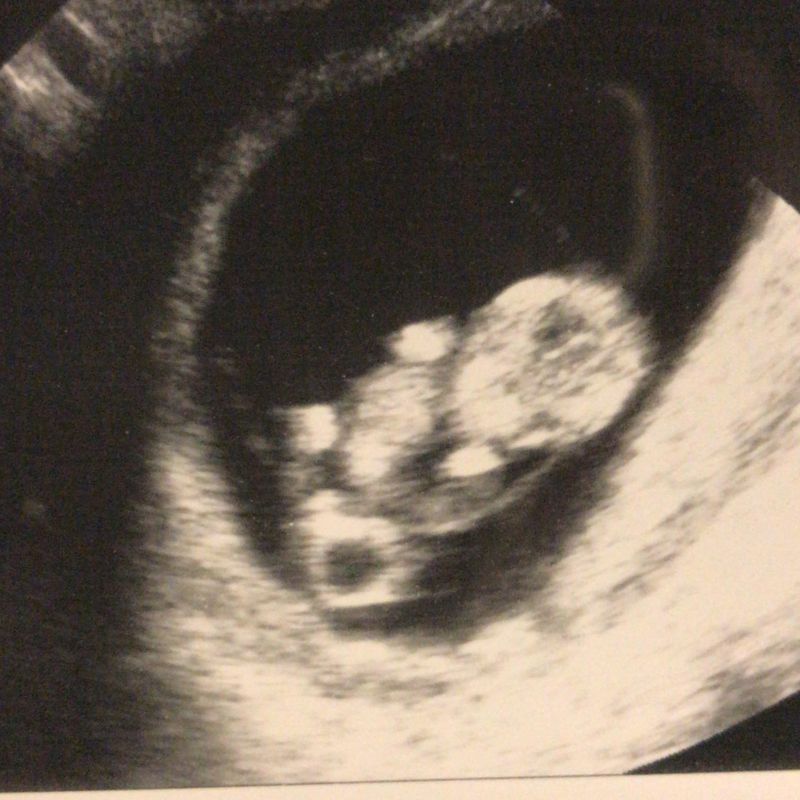

Begin november zijn we voor de eerste afspraak bij de klinisch verloskundige geweest. Jeetje, wat kwam er veel op ons af. Allereerst hebben we even gekeken naar ins baby’tje. Een mooi kloppend hartje en een termijn van ongeveer 8 weken. De verloskundige zei dat het fijn was om te zien, gezien de voorgeschiedenis, dat het er in ieder geval maar een is! Daar waren we zelf ook erg blij mee, want een eventuele tweeling had ons nog meer zorgen bezorgd. Verder hebben we ook heel Sid z’n avontuur besproken, hoe het gegaan is en de reis die hij gemaakt heeft om te komen waar hij nu is, dat vond ik fijn. Ik heb aangegeven dat, mocht het weer gebeuren, we graag naar Veldhoven zouden gaan. Verder hebben we ook de komende periode vol afspraken besproken. Ik vond dat er veel werd gedaan voor en met ons. Alles voor een mooi doel, namelijk een voldragen zwangerschap. Wat zou dat bijzonder zijn! Al met al kreeg ik een goed gevoel bij dat we zo goed gevolgd werden.

Ik kreeg bloedingen

Halverwege november waren daar een aantal dagen met bloedingen waardoor het doemdenken bij mij de overhand kreeg. Ik heb toch maar de afdeling gynaecologie gebeld en ik mocht even langskomen ter geruststelling. Een fijne echo volgde, waarop alles goed was. De opluchting was groot. Mijn ongerustheid werd begrepen en dat gaf rust.

De termijnecho

Eind november hadden we de termijn echo bij het echobureau met daarna een consult. Ik was 10+5 zwanger en de uitgerekende datum was 17 juni 2018. Aan de hand van dit consult besloten we voor de NIPT te gaan. Ook besloten we om vanaf week 16 injecties te zetten en daarnaast mee te doen met de studie met aspirine. Ze denken dat ze vroeggeboorte met 30% terug kunnen dringen door middel van een kinderdosis aspirine per dag. Helaas weten we niet of ik echt aspirine krijg of de placebo.